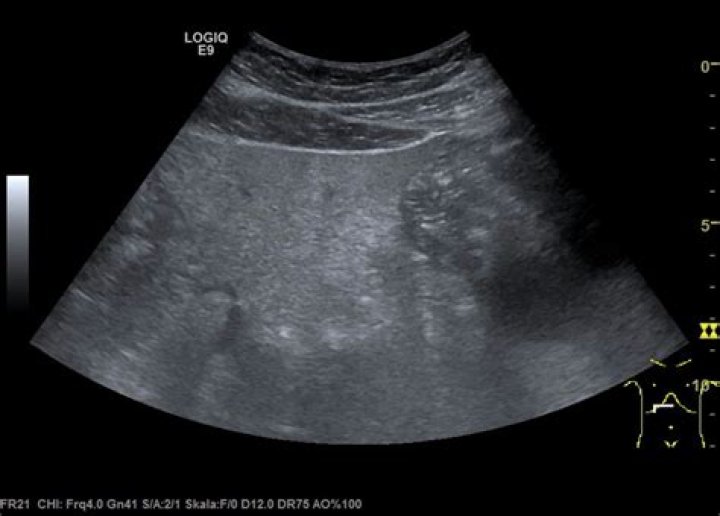

How does pancreatitis appear on ultrasound?

Sonographic findings of acute pancreatitis can be subtle and can include changes in pancreatic echogenicity, glandular enlargement, pancreatic duct dilation, and peripancreatic fluid [11]. Enlargement of the pancreas as well as hypoechoic or heterogeneous echotexture [8] is caused by associated interstitial edema (Fig.